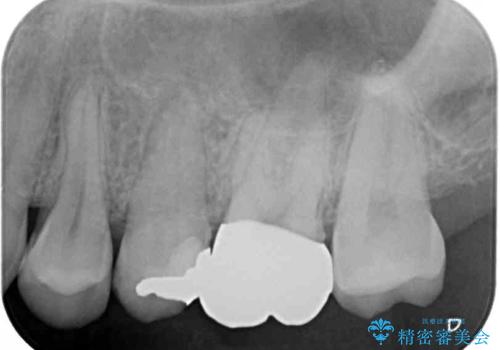

- 奥歯の虫歯と銀歯を気にして来院された患者様です。

セラミックインレーおよびセラミッククラウンによる治療を希望されましたが、虫歯となっている歯は神経近くにまで蝕まれていたため、長期的な予後を鑑みて、PGAインレー(プラチナゴールドインレー)にて修復することとしました。

ゴールドインレーを装着するまでは、金属色が目立ってしまうのではないかと心配されていましたが、表からは見えない位置にあること、銀歯と異なり目立つ色ではないことから、審美的な問題はありませんでした。